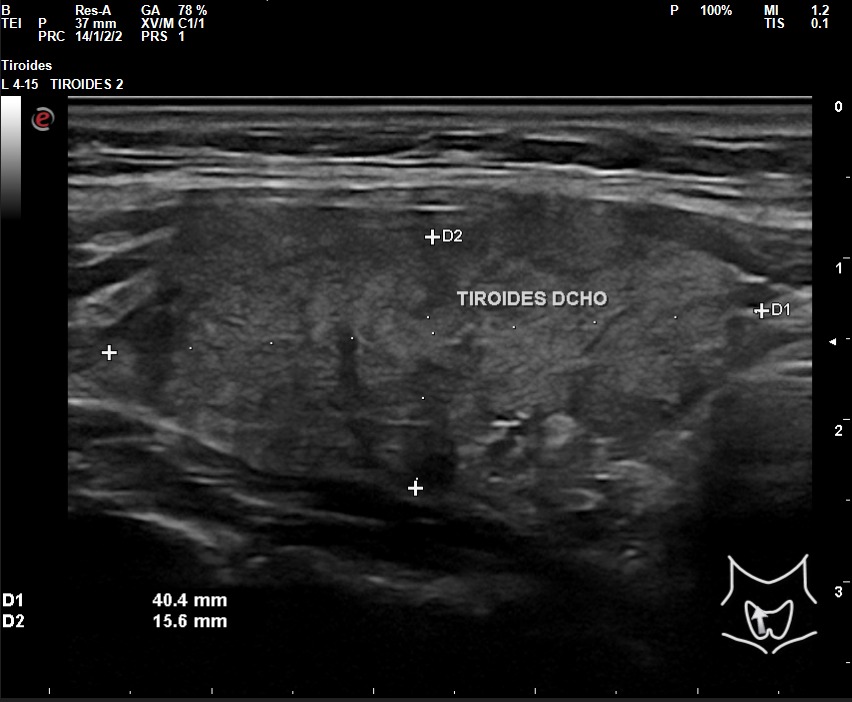

A la exploración ecográfica se observa en lóbulo tiroideo derecho áreas irregulares hipoecoicas sensibles a la sonopalpación con el transductor, con un ligero incremento de la actividad Doppler, asociado a la presencia de adenopatías de características reactivas y/o inflamatorias.

Los hallazgos ecográficos en otro contexto clínico, sin el dolor a la sonopalpación y sin el antecedente de posible viriasis previa, podrían ser muy parecidos al de un nódulo tiroideo sospechoso de malignidad: hipoecoico, márgenes irregulares, etc.